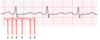

Which segments make up the PR interval?

1 + 2

Which segments make up the QT interval?

3 + 4 + 5

Which ECG feature is labeled by segment 2?

PR Segment